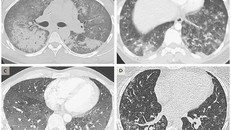

(Ngày Nay) - Cậu bé 2 tuổi được đưa đi khám vì ho kéo dài, bác sĩ đã phát hoảng khi kết quả chụp phim cho thấy xương ức và một nửa các xương sườn bên trái của bé đã biến mất hoàn toàn do căn bệnh lạ.